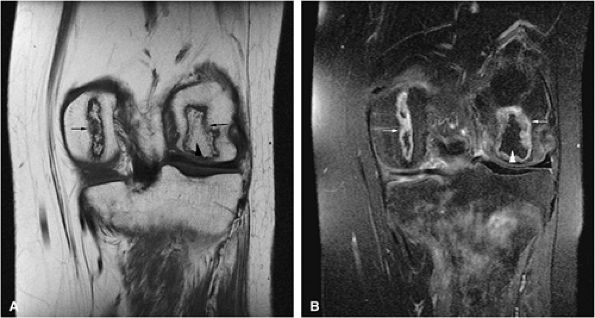

FIGURE 13.31 ● High-grade lymphoma of bone. (A) Marrow involvement of the distal femur is hypointense on a coronal T1-weighted image (arrows). (B) The extent of marrow involvement is better seen on a sagittal STIR image (white arrows). Peritumoral edema and soft-tissue component are hyperintense (black arrowheads). (C) Large associated soft-tissue component is seen on an axial fat-suppressed T2-weighted image (arrows). (D) Axial CT image obtained for biopsy shows destruction of the distal femur with pathological fracture (arrow). (E) Osseous destruction with soft-tissue component is demonstrated (arrows).